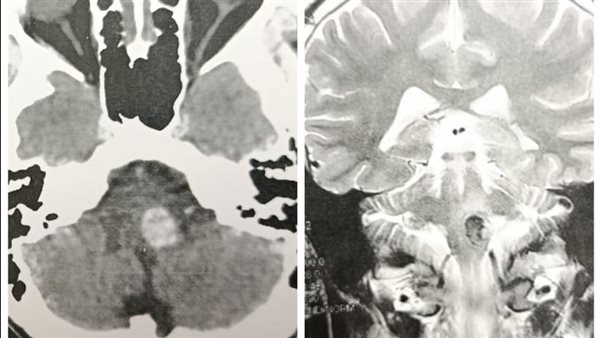

نجح فريق طبي متخصص بقسم جراحة المخ والأعصاب، بجامعة أسيوط، في إجراء واحدة من أدق وأخطر الجراحات الميكروسكوبية، باستئصال ورم وعائي (وحمة دموية - Cavernoma) من جذع المخ لشاب، وهي المنطقة التي تُعرف طبيا بأنها أكثر مناطق الجهاز العصبي حساسية.

كان مستشفى الأمراض العصبية والنفسية وجراحة المخ والأعصاب برئاسة الدكتور طارق راجح، استقبل شاب يبلغ من العمر 23 عاما، يعاني من وحمة دموية من جذع مخ، تسببت له بأعراض عصبية متعددة شملت صداع شديد، واضطراب في الاتزان، وضعفا بالأطراف، وتأثر ببعض الأعصاب المخية، وتكمن صعوبة العملية في الموقع التشريحي للورم، حيث يعتبر جذع المخ الممر الرئيسي لمراكز التحكم في التنفس، الحركة، الاتزان، والأعصاب المخية، وهو ما يجعل التدخل الجراحي في هذه المنطقة بالغ الخطورة، نظرًا لأن أي خطأ غير مقصود قد يؤدي إلى مضاعفات دائمة.

واختار الفريق الطبي مدخل جراحي آمن للوصول لعمق المخ، وذلك من خلال استخدام أحدث تقنيات المجهر الجراحي للتحكم في الأوعية الدقيقة دون الإضرار بالأنسجة العصبية المحيطة بالورم.